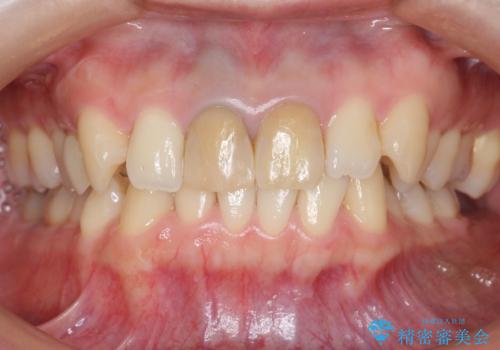

神経の方は問題なさそうだったため、患者様の希望でやりなおさず、土台とセラミック治療を行いました。

- 32万円(税別) 上顎両側1 ファイバーコア、仮歯、ジルコニアクラウン(スペシャル)費用は治療当時の料金となります

歯茎の黒ずみに関しては、中の歯の根が変色して透けている状態のため、変えることは難しいです。

笑っても歯肉が見えにくい方でしたので、問題ありませんでした。